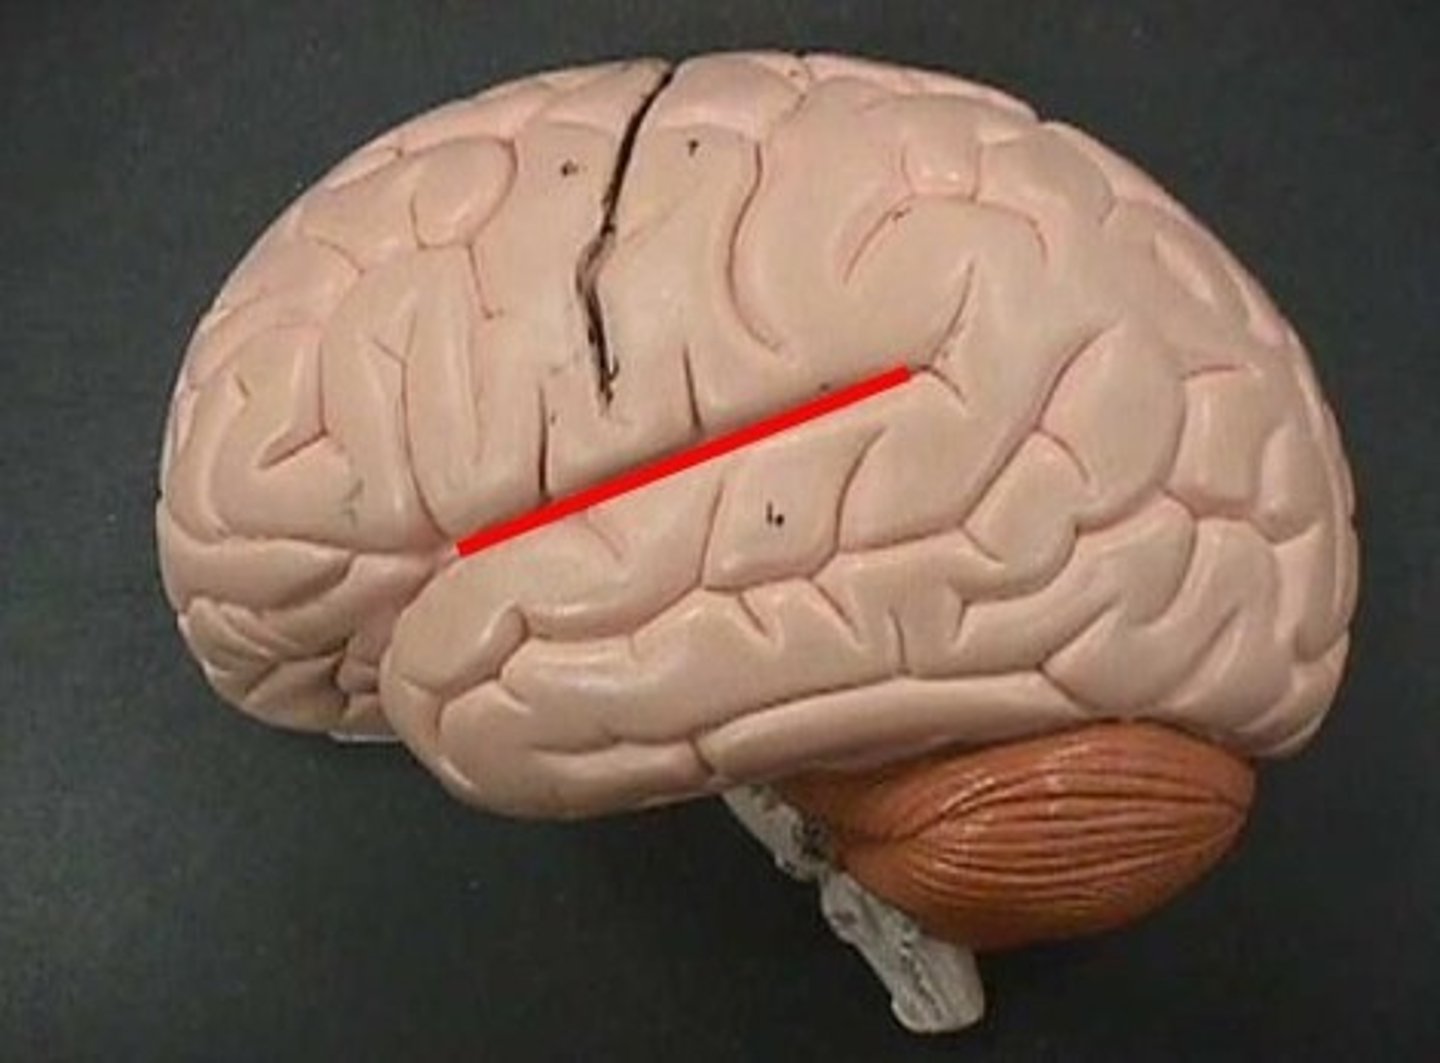

lateral sulci